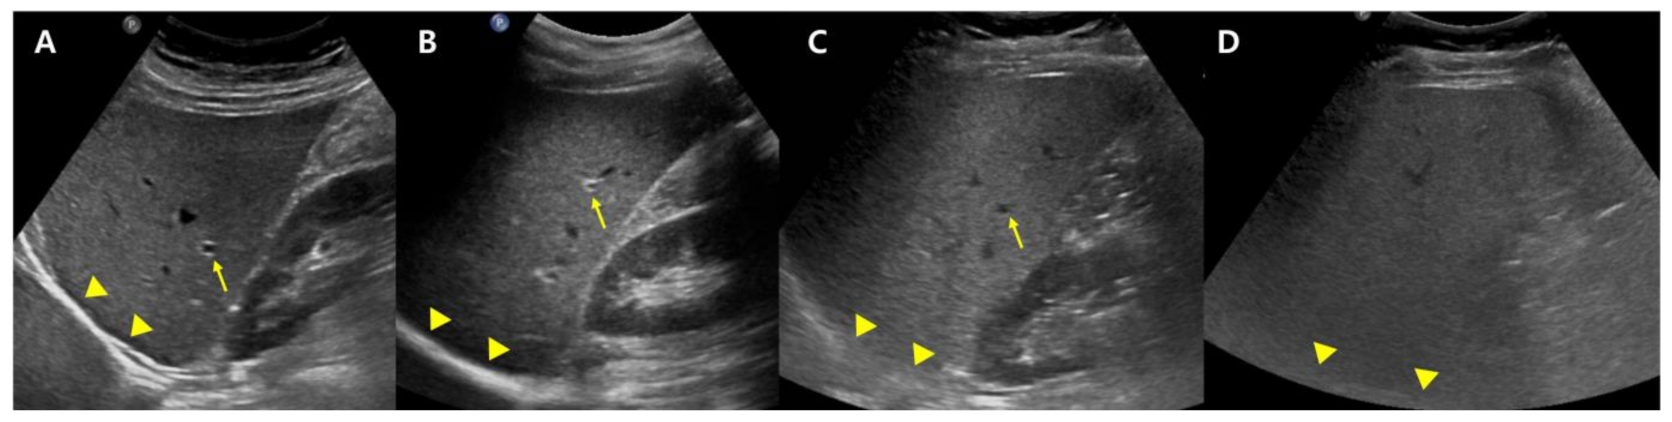

B-mode US allows an estimate of steatosis severity according to the subjective examination of sonographic patterns [20]. The severity is generally categorized as absent, mild, moderate, and severe. Mild hepatic steatosis is seen as a more diffuse increase in liver echogenicity than the renal cortex, moderate hepatic steatosis is seen as an increase in liver echogenicity with impaired visibility of the diaphragm and portal vein wall, and severe hepatic steatosis is seen as a large increase in liver echogenicity and poor visualization of the diaphragm, portal vein wall, and posterior regions of the right liver lobe (Figure 1).

Figure 1.

Conventional US examination for evaluation of hepatic steatosis: normal (A), mild (B), moderate (C), and severe (D) hepatic steatosis. The vessel (arrow) and diaphragm (arrowhead) are well distinguishable in a normal liver (A). Liver parenchymal echogenicity is increased compared with renal cortical echogenicity in mild hepatic steatosis (B). In moderate hepatic steatosis (C), the vessel wall echo becomes obscured (arrow), and the diaphragm is partially visible (arrowhead). Due to a marked increase in liver echogenicity in severe hepatic steatosis (D), there is blurring and poor visualization of the diaphragm (arrowhead), as well as deep posterior parts of the right liver lobe.